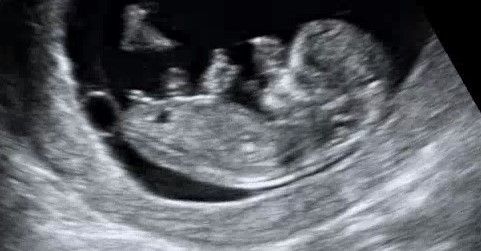

Девчушка 🎀

Если не секрет узнали кто у Вас? У меня узи очень похоже с Вашим.думаю девочка